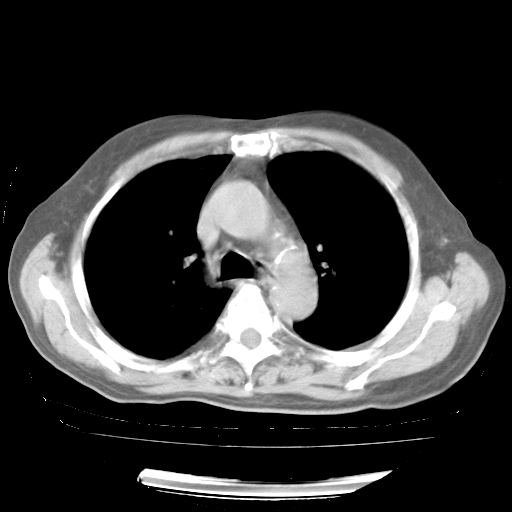

4月28日肺部CT——再次出现类似去年5月9日——磨玻璃样、间有“粟粒样”改变。